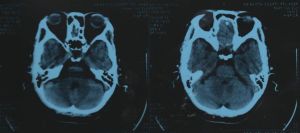

腦CT 2、腦CT可明確顯示顱內腫瘤的數目、部位、大小、輪廓、密度、瘤內出血、鈣化以及擴散程度。

3、腦CT對腦血管疾病診斷準確,並有助於確定治療方案。

4、腦CT對顱腦損傷可分辨血腫的大小、形態、範圍、數目及其鄰近腦組織壓迫情況。觀察有無亞急性或慢性顱內血腫的存在,判斷顱腦損傷的吸收、縮小情況,亦可顯示腦軟化、腦萎縮、腦積水及腦穿通畸形等後遺症。